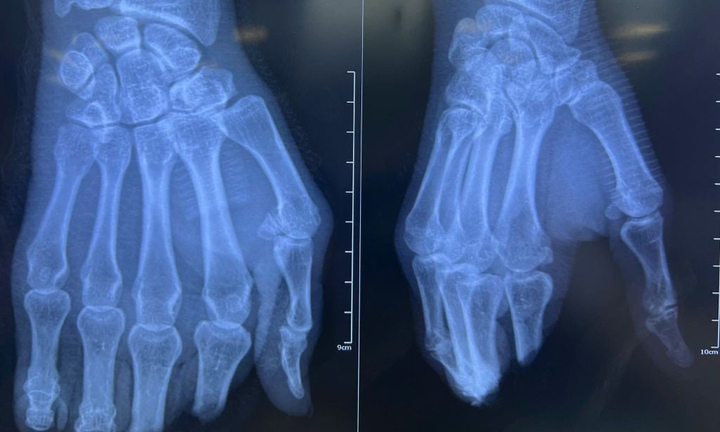

Ngày 17/3, Bệnh viện Nhân dân 115 phẫu thuật vi phẫu cứu 4 ngón tay bị đứt lìa hoàn toàn cho nam bệnh nhân gặp tai nạn máy cắt giấy.

Thời gian qua, rất nhiều trường hợp tại TP.HCM nhập viện với tình trạng đứt rời ngón tay hoặc cánh tay, phần lớn các bệnh nhân này đều ở độ tuổi rất trẻ, là công nhân của các xưởng sản xuất.